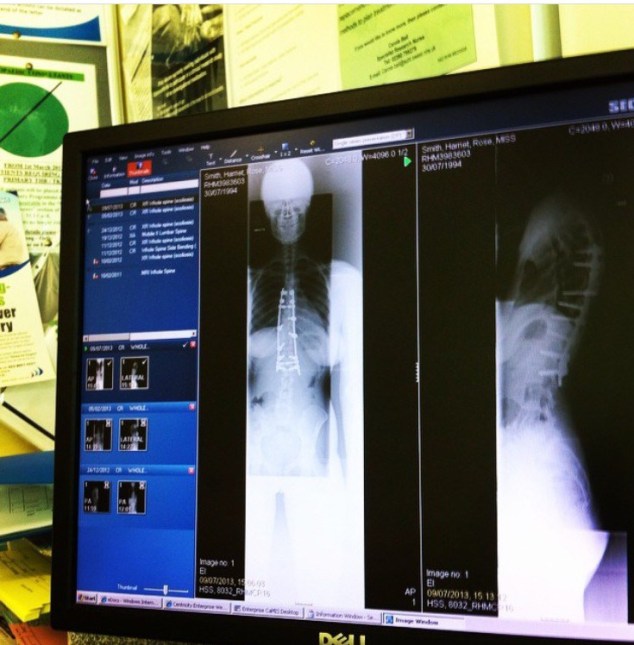

Unfortunately, Harriet’s scoliosis curve was progressive- her curvature was deemed “severe” and she was therefore offered the option of having spinal fusion surgery. In spinal fusion for scoliosis, titanium rods and bolts are attached to the curved part of the backbone and the spine is straightened. Small pieces of bone are then put over the spine. The bone pieces will grow together with the spinal bone, fusing it into the proper position. Spinal fusion is major surgery that usually takes several hours to complete.